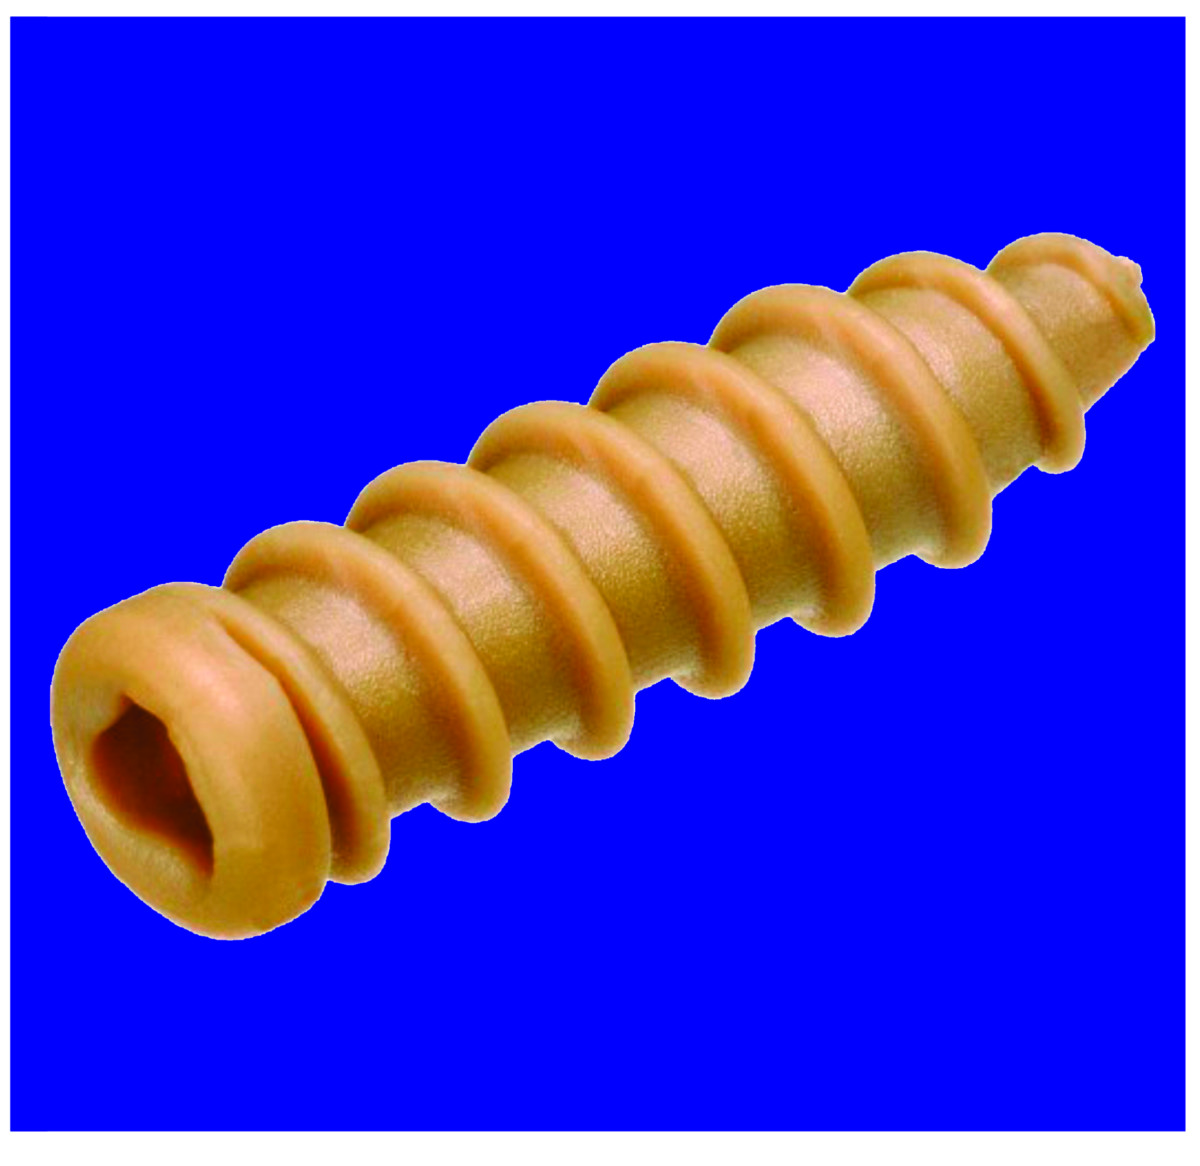

Matéria Prima: PEEK (Poli-Éter-Éter-Cetona com adição de 6% de Sulfato de Bário, para uso medicinal), termoplástico biocompatível, especifico para uso médico.

É um parafuso canulado, de uso único, produzido em polímero termoplástico a base de Poli-Eter-Eter-Cetona, extremamente biocompatível, com adição de 6% de sulfato de bário em sua composição que facilita a sua visualização em exames de imagem.